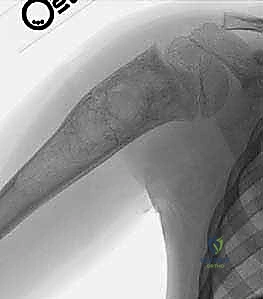

تُظهر هذه الأشعة السينية كيس عظم متمدد (ABC). لاحظ التوسع الكبير في العظم وترقق القشرة العظمية مقارنة بالكيس أحادي الغرفة.

على النقيض تماماً من الـ UBC، يُعد كيس العظم المتمدد آفة حميدة ولكنها نشطة جداً وأحياناً عدوانية موضعياً. سمي بـ "المتمدد" لأنه يسبب انتفاخاً وتوسعاً ملحوظاً في العظم المصاب، وكأنه بالون ينتفخ داخل العظم.

* التكوين النسيجي: لا يحتوي على سائل صافٍ، بل يحتوي على مساحات كيسية متعددة مملوءة بالدم. من الناحية المجهرية، هذه المساحات ليست أوعية دموية حقيقية (تفتقر للبطانة الوعائية)، بل تفصلها حواجز ليفية تحتوي على خلايا عملاقة (Giant Cells) وعظم غير ناضج. هذا التمييز النسيجي حاسم لفهم سبب نزيفها الشديد أثناء الجراحة وطبيعتها العدوانية.

في الـ ABC، تظهر الآفة غير مركزية، متمددة، وتدفع قشرة العظم للخارج لتصبح رقيقة جداً مثل "قشرة البيضة".